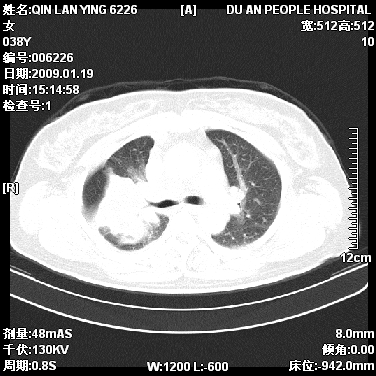

女,38岁,胸疼1个月。wbc:1万4

1)右肺中央型肺癌并右肺上叶阻塞性肺炎、节段性肺不张,纵隔淋巴结转移、右侧胸膜转移、肝脏转移。2)右侧胸腔少量积液。

本病例有几个容易诊断的地方:1、右肺上叶前段支气管闭塞,肺不张。2、淋巴结明显肿大。3、肝脏多个类圆形低密度影呈“牛眼征”改变,高度提示转移。

从影像学角度分析      右肺上叶中央型肺癌,并阻塞性不张、肺炎,纵隔淋巴结、膈顶淋巴结转移。

肝内两个大小不等低密度结节,内可见更低密度影,首先考虑肝内转移瘤,但联想到患者wbc1万4,建议楼主还是做个增强比较明确,除外肝脓肿的可能。